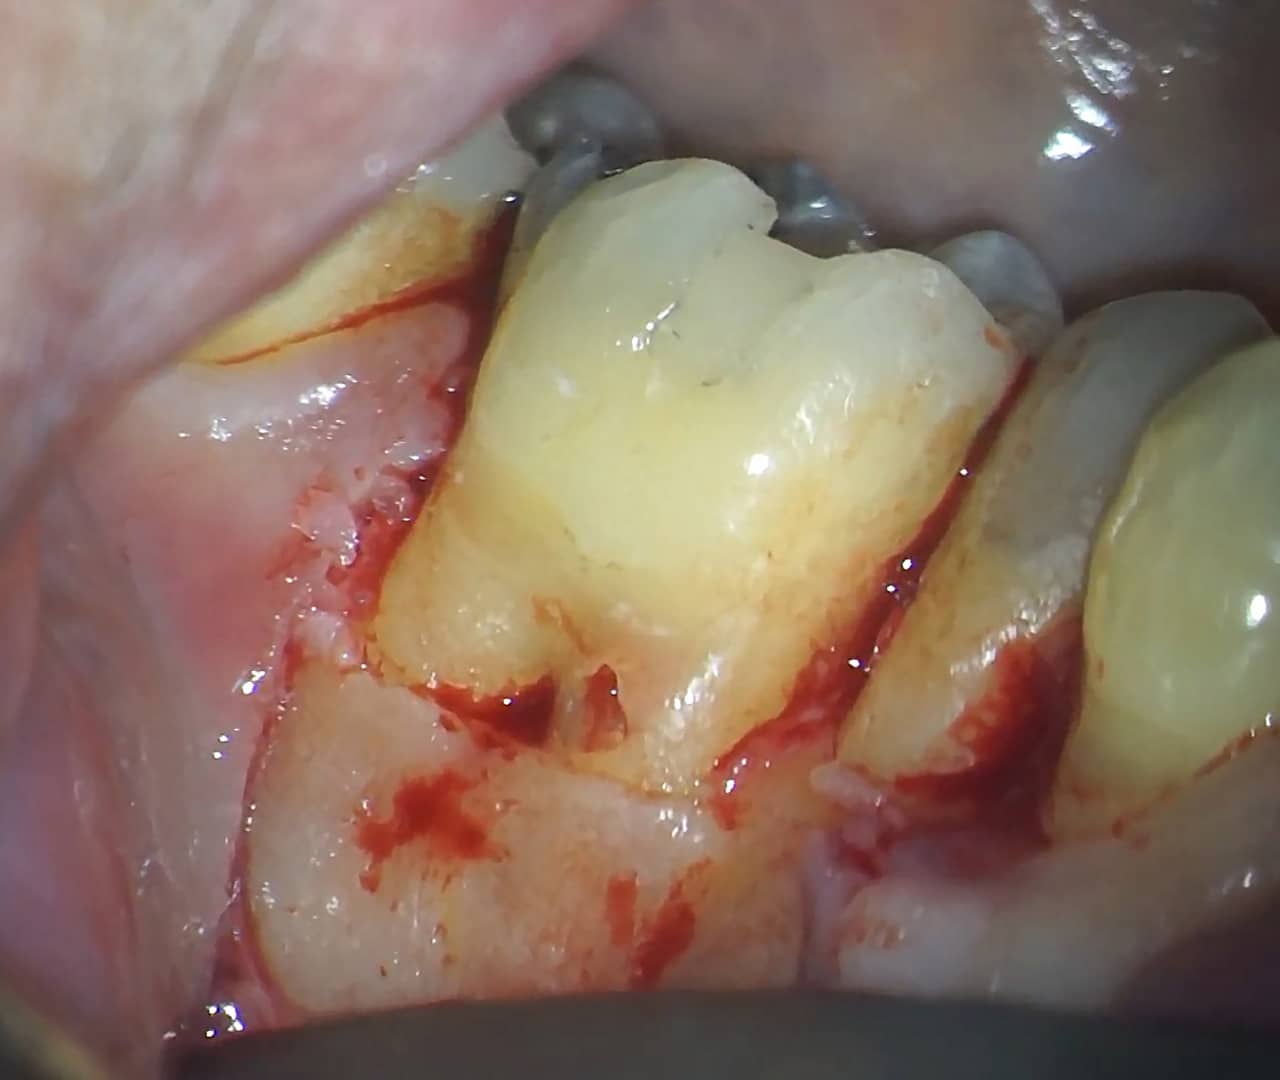

Dans ce troisième temps, l’objectif est d’atteindre la lésion de résorption afin de la cureter correctement, convenablement et entièrement. Pour ce faire, un lambeau de petite étendue est levé avec une incision de décharge en mésial et une incision en circulaire sur la dent 36 uniquement. Le lambeau est récliné, la lésion est très vite mise en évidence (Fig.15).

Elle est alors nettoyée avec un insert ultra-sonore diamanté, courbé, de chirurgie endodontique (insert RD25, Woodpecker, Chine) (Fig.16). Le curetage est minutieux et permet, à un moment donné, de mettre en évidence la gutta percha que l’on reconnaît au sein du canal.

Fig.15 : Vue de la lésion de résorption sur la racine mésiale de la dent, après avoir décollé le lambeau de pleine épaisseur.